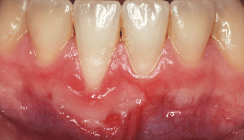

Weichgewebsmanagement

Die Implantate wurden nach einem Vierteljahr in Kombination mit Weichgewebsmanagement freigelegt. Der sowohl bei der Augmentation als auch bei der Implantation notwendige spannungsfreie Wundverschluss hat zur Konsequenz, dass sich die mukogingivale Grenze nach oral verschiebt und das Vestibulum abflacht. Zur Korrektur des entstandenen Defizits an fixierter und keratinisierter Gingiva wurde die Freilegung durch einen apikalen Verschiebelappen in Kombination mit Schleimhauttransplantationen durchgeführt (Abb. 21 und 22). Beim apikalen Verschiebelappen wird ein teilschichtiger Lappen bis über die mukogingivale Grenze nach bukkal präpariert und bukkal der Implantate vernäht (Abb. 22).31 Die Technik führt zu einem Gewinn an keratinisierter und fixierter Gingiva bukkal der Implantate.32–34